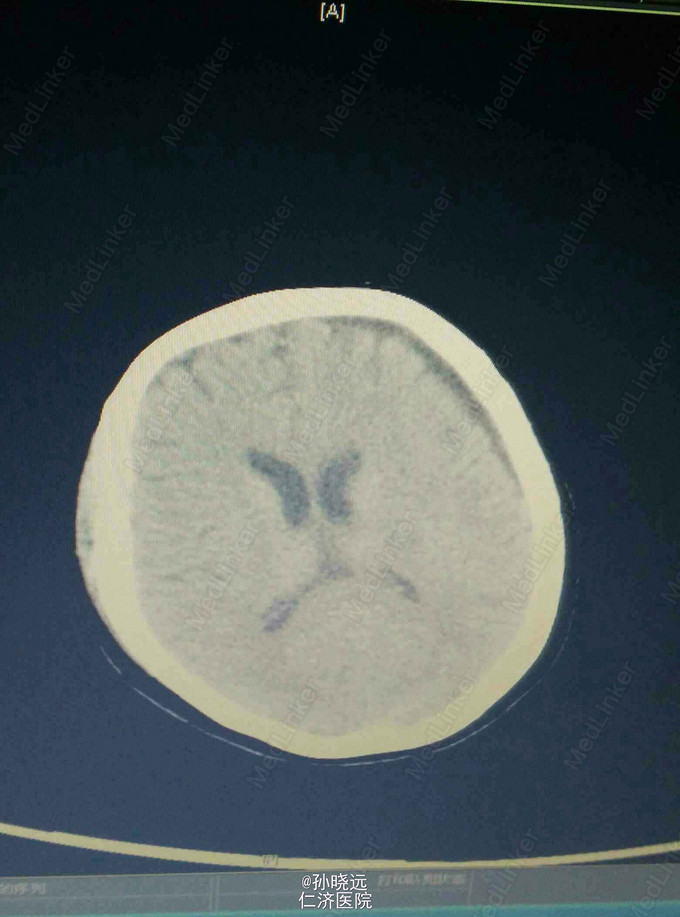

中年女性。主诉:头晕三天,发热伴神志不清1天。 患者于三天前出现持续性头晕,无恶心、呕吐,无视物旋转,来院就诊,查头颅MRI未见异常,予桂哌齐特、长春西汀、硫辛酸治疗,症状无好转。1天前出现高热,最高39.5℃,无咳嗽、气促,再次来院就诊,查血常规:WBC:5.85*10^9/L,N:71.8%,CRP正常,予退热,阿奇霉素等治疗,今日凌晨出现神志不清,无抽搐、恶心、呕吐,头颅CT示两侧颞底部不规则斑点样密度增高影并周围低密度灶,考虑脑炎合并灶性出血,予更昔洛韦、醒脑静、喜炎平、奥美拉唑、甘露醇治疗。后出现氧饱和度下降,予气管插管有创呼吸机辅助通气。 既往史:曾有高血压病史,未应用降压药。

诊断:脑炎。脑出血。 治疗:甲强龙抗炎,更昔洛韦,青霉素钠抗感染,降压,甘露醇、甘油果糖、白蛋白、拖拉塞米里降颅压,呼吸机辅助通气等对症治疗。

腰穿是: 脑脊液生化:葡萄糖:12.18mmol/L,CL:110.9mmol/L,蛋白:222.4mg/dl, 脑脊液常规:淡黄,微混。红细胞:1000*10^6/L,白细胞:1059*10^6/L,潘氏试验阳性(++++),嗜中性粒细胞12%,淋巴细胞:80%,单核细胞8%,凝块无,细菌未找到。 予加用血必净,加强抗感染等治疗。 患者目前仍昏迷,正进行高压氧仓治疗。这是最近一次复查的头颅CT。